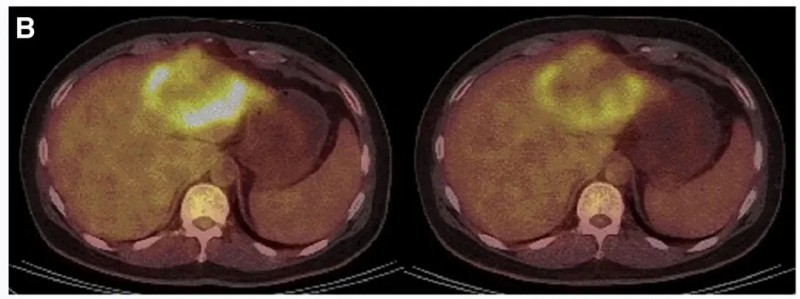

结果显示:10例既往治疗进展(PD)的患者中,7例经CAR-T治疗后病情稳定(SD)、肿瘤直径微变,其中P3、P5的稳定状态超30周(7.5个月)。两例典型病例疗效尤为显著:P10接受DL4剂量治疗后,MRI证实肝内一处病灶缩小(详见下图C);P9-2经PET/CT检查显示肿瘤活动减弱、代谢活性显著降低(详见下图B)。

▼P9-2患者在CAR-T输注前(左图)、治疗4周后(右图)的PET/CT对比

▲图源“Molecular Therapy”,版权归原作者所有,如无意中侵犯了知识产权,请联系我们删除